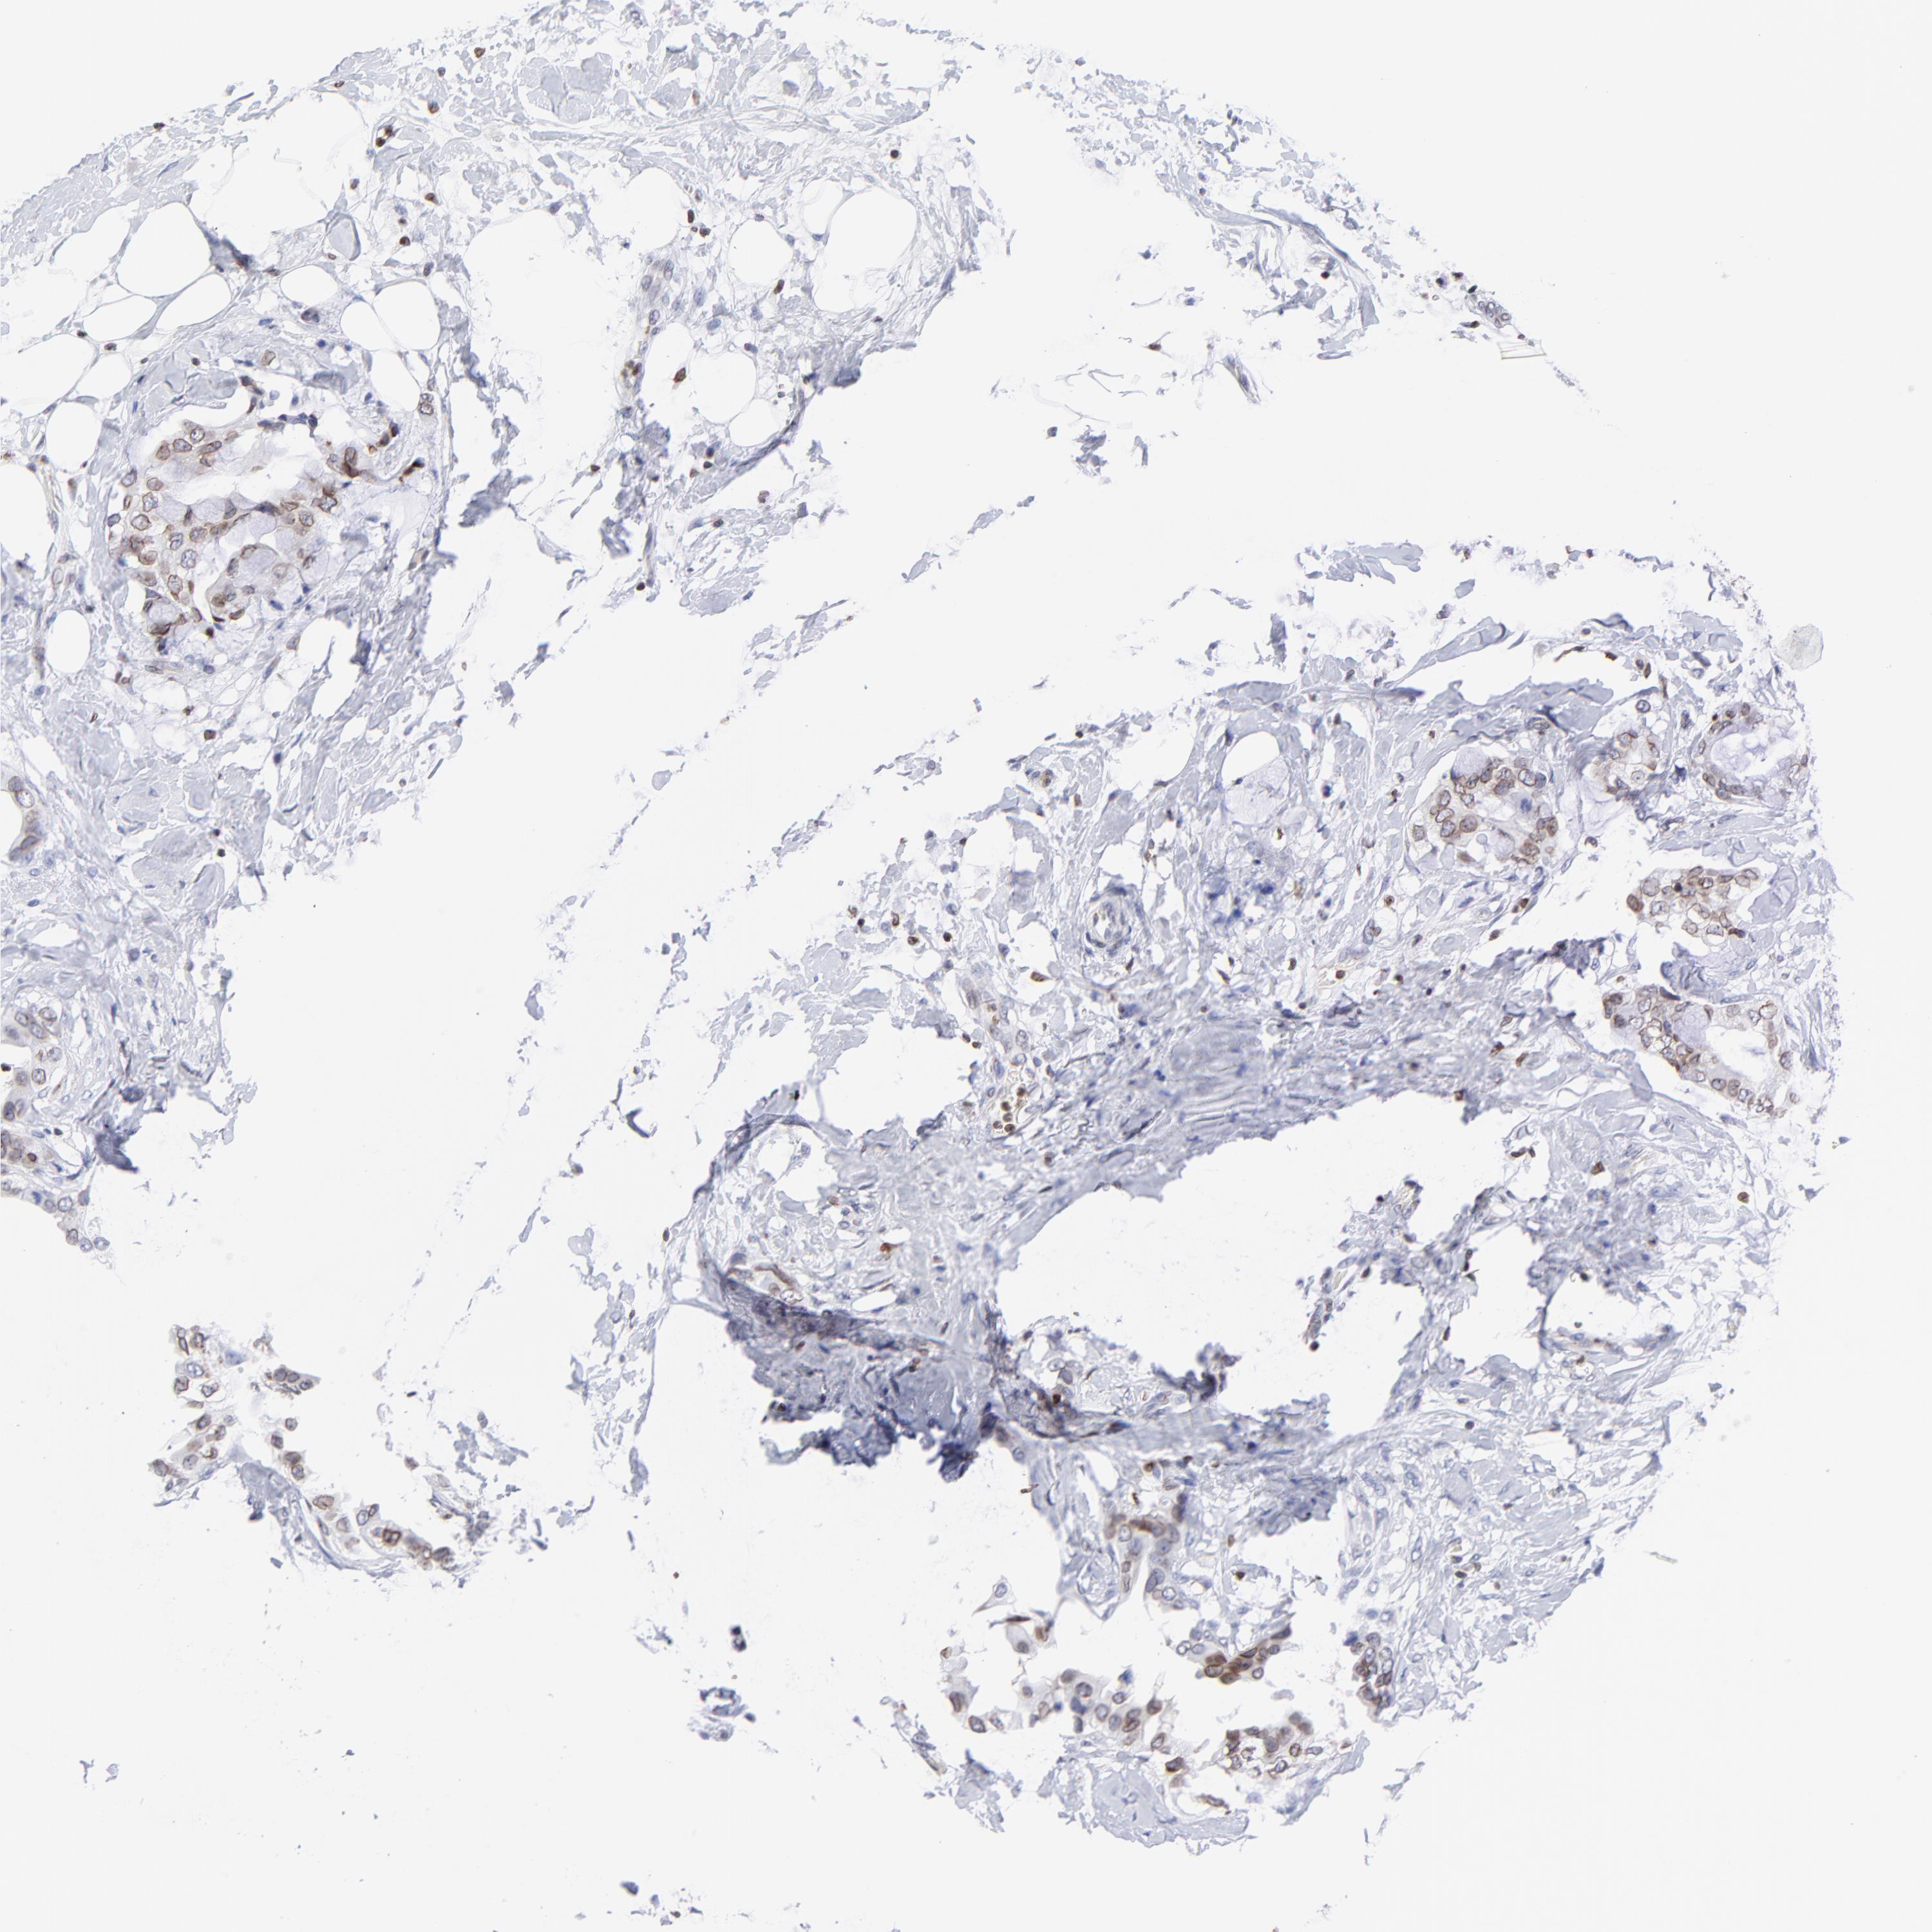

BRCA TCGA BRCA VALIDATION PROTEIN EXPRESSION

ANTIBODIES

AND

VALIDATION